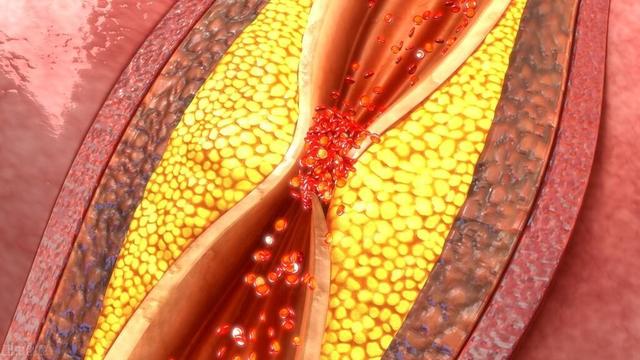

- a. 動脈硬化:これが最も一般的な原因である。脳につながる動脈の開存性と脳内の動脈の開存性の両方に影響を及ぼす。頸動脈は脳に血液を供給する最も重要な動脈のひとつである。アテローム性動脈硬化症は頸動脈にプラークを形成する。アテローム性動脈硬化症は頸動脈にプラークの形成をもたらし、プラークの形成は血管の内腔の狭窄をもたらし、内腔の狭窄は脳への血流不足をもたらす。

動脈硬化は全身の動脈に影響を及ぼすが、脳内の動脈は免れない。その結果、脳への血流が悪くなり、脳内の血流も悪くなる。二重の影響が脳への血液供給に影響し、脳への血液供給が不足する。動脈硬化は高齢者の血液供給不足の最も重要な原因である。

血管が原因。血管壁の損傷、内腔の狭窄、血管攣縮などである。脳動脈硬化、壁に硬化したプラークの形成、内腔の狭小化、菲薄化、血管抵抗の増大による血流量の減少、特に脳を長時間にわたって酷使し続けた後に、脳血液の供給と相対的に起こることが多い。

2、高脂血症高脂血症、特に高LDL、高コレステロールの患者における最も重要な危険性は、動脈硬化を引き起こし、血管の内壁にプラークが形成されることである。

一般に虚血は、血管にプラークや硬化などの変化が生じ、血流が変化することで起こる。

頸動脈などのプラークは、血流が通過するにつれて小さくなるため、脳への血液供給不足につながる。この病変は超音波検査で発見することができ、一般的な治療方針は、血圧をコントロールし、血中脂質を下げることで、プラークが大きくなるのを防ぎ、腫瘍性プラークを予防することを目指すが、プラークを除去することはできない。プラークがあまりに大きく、脳への血液供給に深刻な影響を及ぼすような場合には、外科的切除も選択肢となる。

アテローム性動脈硬化症、高脂血症、高血圧、糖尿病などは、内頸動脈の内腔を狭くし、弾力性を低下させ、血管壁に脂質が沈着してアテローム性動脈硬化斑を形成し、アテローム性動脈硬化斑が破裂して出血したり、血栓を形成して脳虚血に至ることがある。